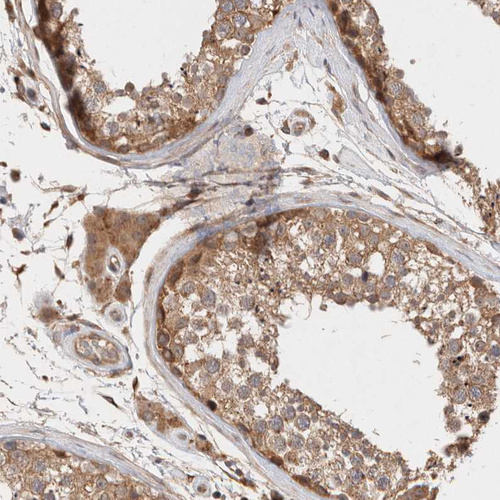

Immunohistochemical staining of human testis shows moderate cytoplasmic positivity in cells in seminiferous ducts.